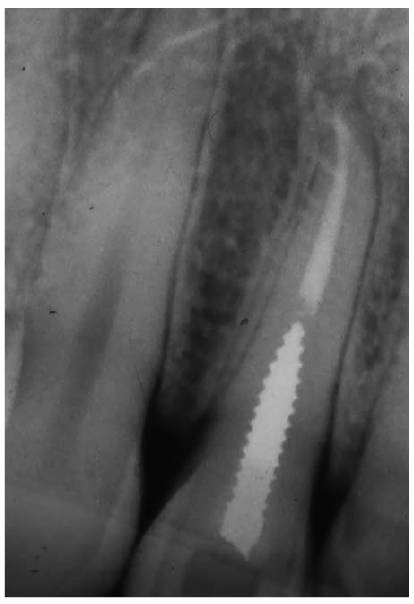

Figure 19-4B: Radiograph of the same tooth showing external resorption.

Figure 19-4C: Pink spot as a result of internal resorption.

Figure 19-4D: Radiograph of the same tooth showing internal resorption.

that has invaded a coronal cavity produced by caries or resorption (Figures 19-4A 19-4B 19-4C, and 19-4D).